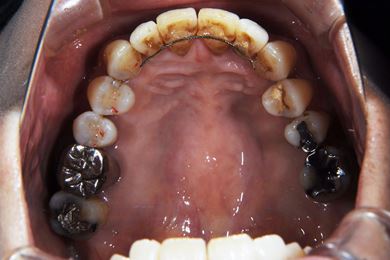

部分矯正治療+骨再生インプラント治療

| 性別/年齢 | 女性 / 52歳 | ||||||||||||||||||||||||||||||||

| 主訴 | 上前歯の歯並びが気になる | ||||||||||||||||||||||||||||||||

| 治療方針 | 全体的に骨が薄く、なるべく歯に負担を立てない治療計画にしました。口元も下げたいため、歯を少し細く削り後ろにさげました。部分矯正後、下顎のインプラントも併用しています。 | ||||||||||||||||||||||||||||||||

| 治療内容 | 部分矯正(唇側矯正ホワイト)、インプラント2本(GBR)、メタルボンドセラミッククラウン3本 | ||||||||||||||||||||||||||||||||

| 総治療費 | 1,573,951円 | ||||||||||||||||||||||||||||||||

| 治療期間 | 11ヶ月 |